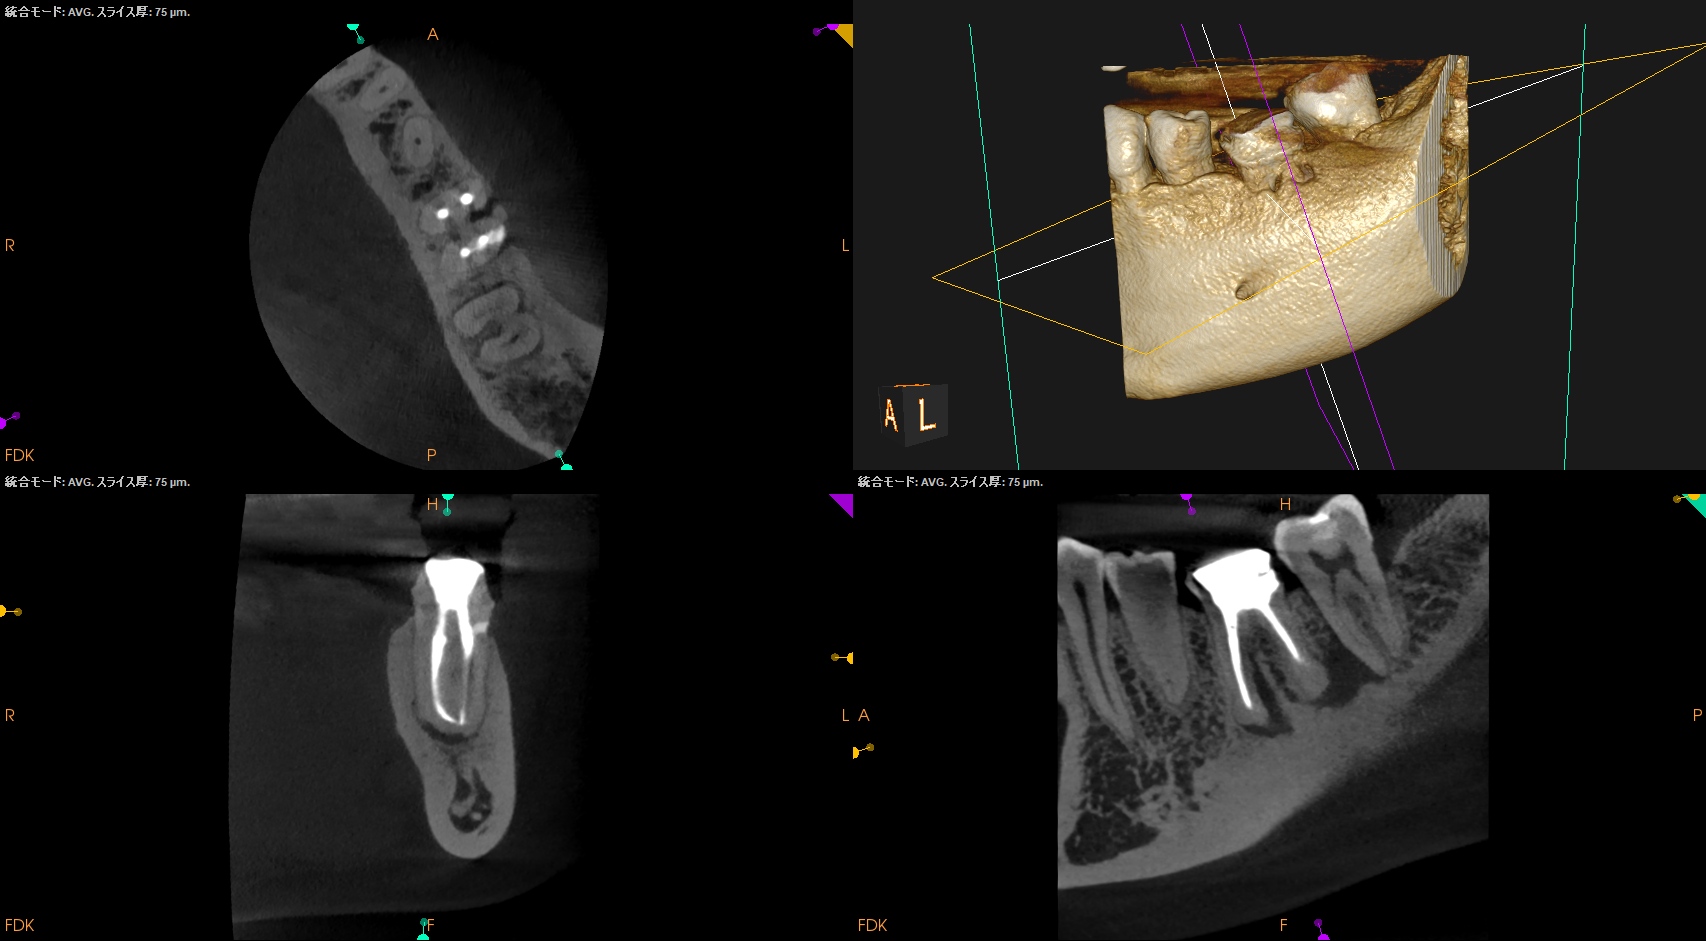

私が気づいたのは、

この絵をみて

違和感

を感じたからである。

穿孔しているのだろうか?とまず思ったが、CBCTをみてそれは穿孔でなく外部吸収の可能性が高いと判断できた。

もはや全ての歯内療法の処置前には必ずCBCTが必要

という法則が成り立つ。

術後にPA, CBCTを撮影した。

MB

ML

DB

DL

B

問題はないだろう。